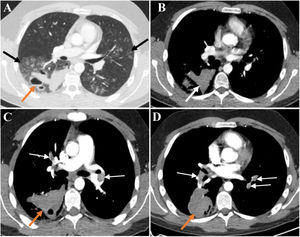

At age 19, the patient needed hospitalization for large-volume haemoptysis. In the previous days, he had intermittent episodes of small-volume haemoptysis preceded by what he described as a “clicking” sensation in the head and, right-sided paraesthesia and mild motor weakness. The chest CT scan (late arterial phase) showed multiple bilateral ground-glass opacities suggestive of diffuse alveolar haemorrhage and large fluid-filled cavities with air-fluid levels suggestive of haemorrhagic cavitation (Fig. 1A/B). Brain and cervical magnetic resonance (MR) imaging, MR angiography of the carotid and vertebrobasilar circulations, including the supra-aortic arches, and electroencephalogram were unremarkable. Despite the decrease in the haemoglobin level relative to baseline (respectively 15.3g/dL and 13.8g/dL), the patient remained hemodynamically stable without respiratory failure. Cough suppressive and antifibrinolytic therapies were initiated. Since the patient did not have any bronchial artery hypertrophy on CT scan and due to the high risk of vascular manipulation, bronchial arteriography was not performed. The surgical risk was also very high; therefore, the patient was not a candidate for thoracic surgery at that time.

(A) Late arterial phase chest CT depicts bilateral peribronchovascular groundglass opacities (GGO), especially in the right lower lobe (black arrows). In the right lower lobe thick-walled cavitary lesions with air-blood levels are also seen (orange arrow). The high density of blood-containing cavities is illustrated in B (white arrow). The GGO translate diffuse alveolar haemorrhage and the cavitary lesions result from the spontaneous rupture of the lung. There was no evidence of haemothorax or pneumothorax.(C and D) CT pulmonary angiographic study shows bilateral pulmonary thromboembolism (white arrows) and enlarged haemorrhagic cavity in the right lower lobe (orange arrows). No signs of pulmonary hypertension or right ventricular strain were present.

A pulmonary CT angiography obtained on day 7 of hospital stay showed extensive bilateral thrombosis and an enlargement of the haemorrhagic parenchymal cavitation, but no actively bleeding arteries (Fig. 1C/D). There were no signs of deep vein thrombosis on Doppler ultrasound examination of the lower limbs. Despite the striking radiological signs, the patient remained asymptomatic. Transthoracic echocardiogram did not show any signs of right ventricular dysfunction, and the Pulmonary Embolism Severity Index (PESI) score was 29 (class I), translating into a low mortality risk.7 Given the high bleeding risk and the low overall risk stratification, hypocoagulation was not prescribed.